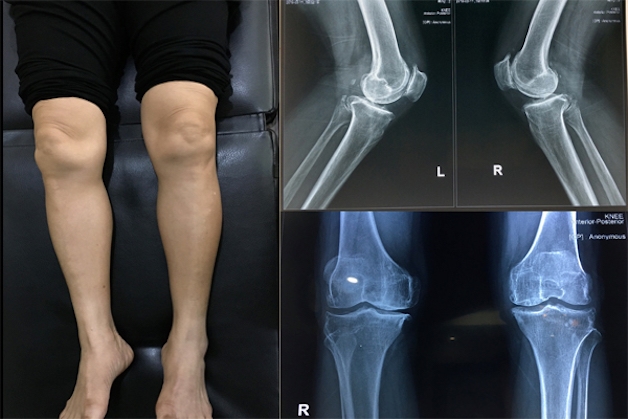

Phẫu thuật thay khớp gối được chỉ định cho đối với những trường hợp bị thoái hóa khớp gối nặng, sụn khớp bị ăn mòn, lệch trục chân nghiêm trọng hoặc bệnh viêm khớp dạng thấp gây phá hủy khớp mà việc tiến hánh điều trị nội khoa không thể khắc phục được.

Thay khớp gối toàn phần thường được chỉ định với các trường hợp bị viêm hoặc thoái hóa khớp một cách nghiêm trọng. Với trường hợp này thì toàn bộ phần khớp gối sẽ được thay thế bằng các vật liệu nhân tạo.

Do mức độ xâm lấn lớn hơn thay khớp gối bán phần cho nên kỹ thuật này thường ẩn chứa nhiều rủi ro và biến chứng hậu phẫu. Tuy nhiên, đa phần các trường hợp sau khi thực hiện thì người bệnh đều nhận thấy các cơn đau thuyên giảm hoàn toàn và khả năng vận động được phục hồi tới 80%.